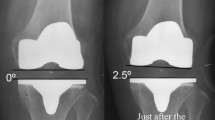

Regarding ligament balancing in extension, the deep layer of the MCL was released within 1 cm from the joint line for bone resection and osteophyte removal. No further extensive medial release was performed to acquire equal medio-lateral joint gap balance, even if lateral laxity was observed. The superficial layer of the MCL, semimembranosus, and posterior oblique ligament were not released. In flexion, gap imbalance was left uncorrected without additional ligament release or bony resection. After setting the femoral component trial, a tensor device was used to measure the joint gap at the center of the knee joint and the varus–valgus angle of the joint gap. The joint gap and the varus–valgus angle were measured applying a distraction force of 178 N with the knee in extension and 90° of flexion (Fig. 1). All components were fixed with Simplex bone cement (Stryker, Kalamazoo, MI, USA). The incision was closed with the knee in 100° of flexion.

The average residual varus–valgus imbalance was 2.8° (SD = 2.8°) varus in extension and 1.3° (SD = 4.0°) varus in flexion. The average varus–valgus angles were kept varus in extension and flexion, respectively (Fig. 3). The average extension gap was smaller than the flexion gap. The average extension and flexion gaps were 9.4 mm (SD = 2.5 mm) and 12.7 mm (SD = 2.8 mm), respectively. The average thickness of polyethylene insert was 10.0 mm (SD = 1.4 mm). The distribution of the laxity in flexion was more variable than in extension (Figs. 4, 5). Analyzing correlation with the alignment and the gap angle and joint laxity, the delta HKA angle had significant correlation with the joint gap angle, and the preoperative TMA and delta TMA had significant correlation with the laxity in extension (Table 2). Larger correction angle of limb alignment showed more varus joint gap in extension, and larger varus deformity and correction angle of the tibia showed more laxity in extension.

In the present study, the same surgical technique was applied for consecutive knees with preoperative varus deformity, and the measurement of the varus–valgus gap angle and joint gap was performed in a uniform manner. Medial release was limited to the deep layer of the MCL even if the varus–valgus imbalance was observed with the aim of neutral coronal alignment. The average varus–valgus imbalance was 2.8° varus in extension and 1.3° varus in flexion. In terms of functional knee phenotype, mechanical alignment target was obtained postoperatively in most of the patients, whereas the preoperative alignment was variable [8].